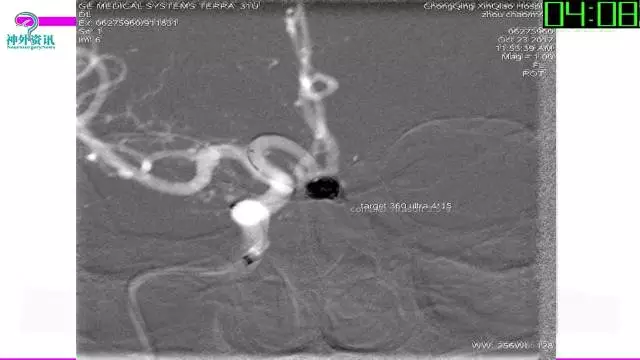

今天为大家分享的是“强生医疗CNV-神经介入专栏”第三十六期,由重庆第三军医大学附属新桥医院神经外科刘俊带来的“Galaxy弹簧圈在不规则动脉瘤中的临床应用”精彩讲课视频及PPT,欢迎观看。文章仅代表作者个人观点,如有不同见解,欢迎同道斧正!